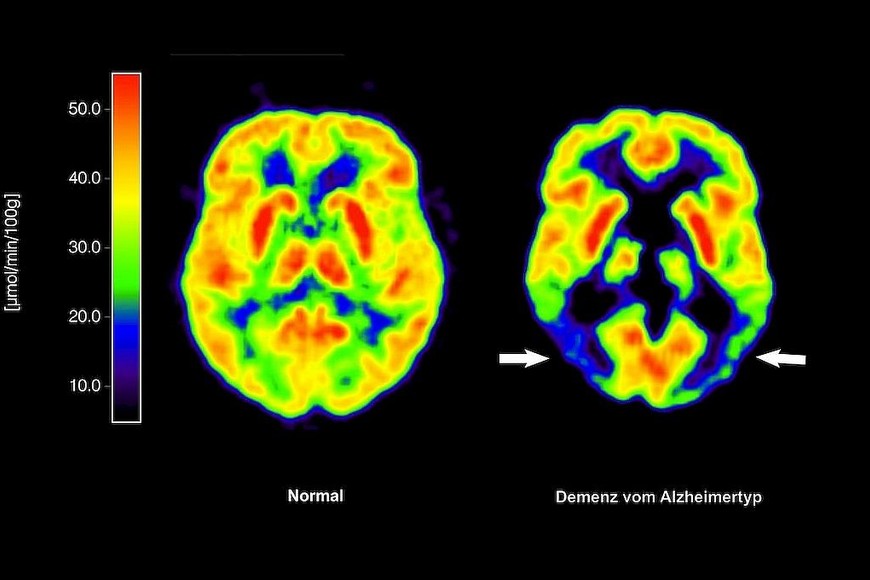

Una alimentación rica en grasas saturadas podría aumentar el riesgo de desarrollar enfermedades neurodegenerativas, como Alzheimer o demencia.